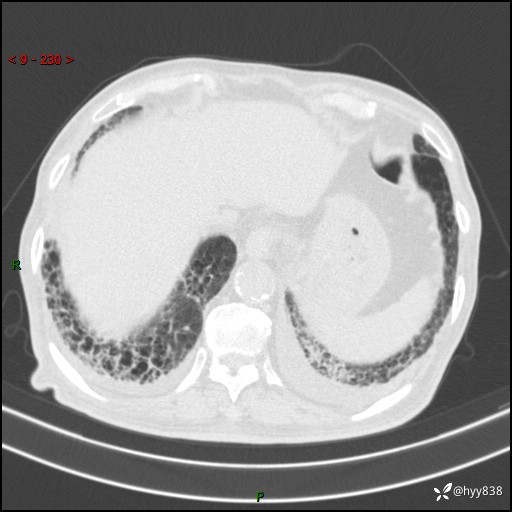

老年男性,间断咳嗽咳痰20余年,加重伴发热1天。呼吸科疑难病例讨论---结果公布

主诉:间断咳嗽咳痰20余年,加重伴发热1天

简要病史:家属代诉患者于20余年前无明显诱因出现咳嗽咳痰,痰为白色泡沫状,未行特殊治疗,不伴胸痛、胸闷、气喘、咳血等不适,1天前上午患者无明显出现发热,查体温39℃,伴咳嗽,咳痰无力,自行予以物理降温对症治疗,今晨2点左右再次出现发热,体温达40℃,自行服用复方氨酚烷胺对症治疗,凌晨3点左右复测体温38.2℃,现患者为求进一步诊治于今日就诊于我院门诊,行胸部CT提示双肺感染,遂以“肺部感染”收入我科。 患者本次起病来精神、食欲、睡眠欠佳,体力下降,体重无明显变化。

辅助检查:CT

临床诊断:感染

讨论:病变性质?

胸部CT平扫